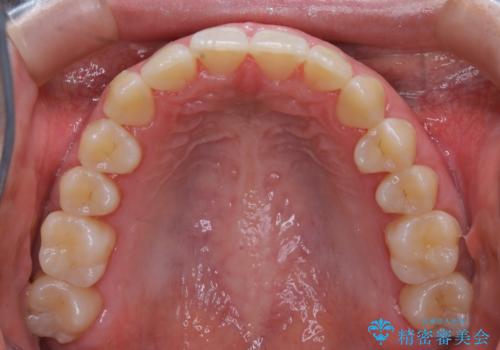

- 初診時、前歯のガタつきを主訴にご来院されました。

精密検査の結果奥歯の噛み合わせのズレからくる前歯のガタつきであることが分かり、患者様と相談した結果、全体をしっかりと治療することをご選択なさったので奥歯から動かして噛み合わせと見た目の両方を治す治療プランとなりました。

下顎の歯は幸いガタつきが少なかったため、下顎を基準とし構成する方針としました。